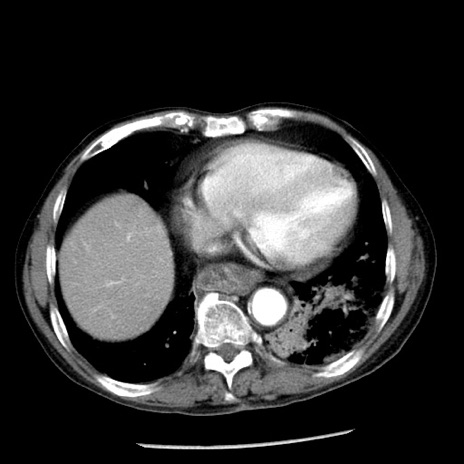

冠状断像

【症例】80歳代男性

【主訴】嘔吐

【現病歴】昨晩2回嘔吐あり、今朝になっても嘔吐あり。来院。

【既往歴】胃潰瘍

【身体所見】意識清明、BT 37.6℃、BP 166/95mmHg、HR 100bpm、SpO2 97%、腹部:平坦・軟、腸蠕動音聴取良好、圧痛なし。

【データ】WBC 21900、CRP 1.46